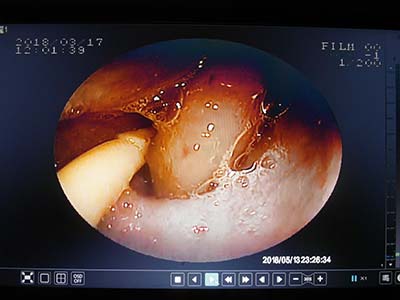

胃中可見邊緣尖銳的骨頭

內視鏡中看到骨頭影像

用工具夾住骨頭